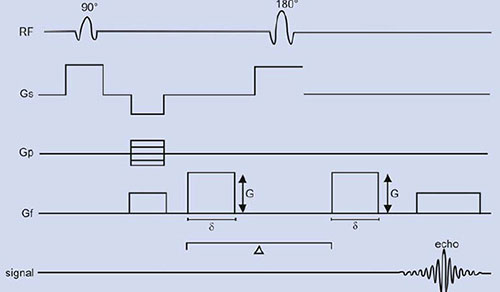

where D is the diffusion coefficient of water. The effect of diffusion on the MR images may be understood using a SE sequence in which a pair of bipolar field gradient pulses is included (Fig. 1.9). The purpose of these gradient pulses is to magnetically ‘phase tag’ the diffusing spins, in much the same way a radiotracer is used to tag a molecule in the more classical diffusion studies in physiology31. In Figure 1.9, the gradient pulse amplitude and duration are denoted by G and δ, respectively, and the interval between gradient pulses by ∆.

For two spins (a1 and a2) diffusing past each other, the first gradient pulse induces a phase shift of the spin transverse magnetization depending on the spin position a1 (spin tagging). Likewise, the second gradient pulse will produce a phase shift, which depends on the spin position a2 at this time (spin untagging). Due to the 180° RF pulse, the net phase shift will be

For static spins (a1 = a2), the bipolar gradient pair has no effect on phase. For moving spins, however, there is a net phase change, which depends on the spin history during the interval ∆ between the gradients that affects the transverse magnetization.

Consider now the macroscopic magnetization arising from the vector sum of the individual diffusing spins, which have different displacement histories (i.e. different phase shifts). Interference between their phases results in attenuation S/So (<1) of the signal amplitude which, for the diffusion process, is given by:

where b is the ‘gradient factor’ characterizing the strength and duration of the applied diffusion gradients and is defined as

Diffusion coefficients, or diffusion lengths, may be evaluated by varying either G or δ and by measuring the slope of the semi-logarithmic plot of (S/So) vs (Gδ)2.